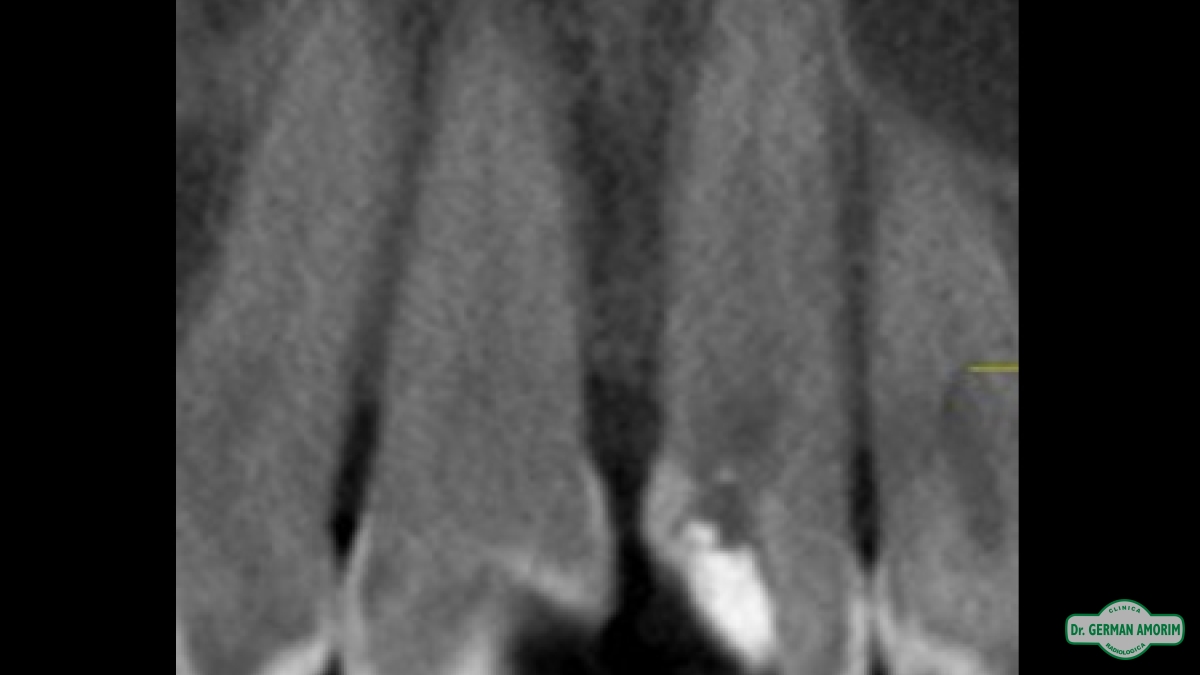

La radiografía tridimensional también tiene mucha utilidad de en Endodoncia como se ve en este caso que detallamos a continuación.

El profesional no podía encontrar el conducto en la radiografía periapical estándar. Al ser bidimensional no lo veía y por eso le indicó una tomografía volumétrica digital (TVD).

En la imagen tridimensional se pudo apreciar dónde estaba el conducto . Como se ve en las imágenes tridimensionales faltó muy poco para hacer una perforación ya que el profesional se estaba yendo hacia vestibular. Gracias a la TVD se pudo identificar y hacer el tratamiento de endodoncia sin problemas.